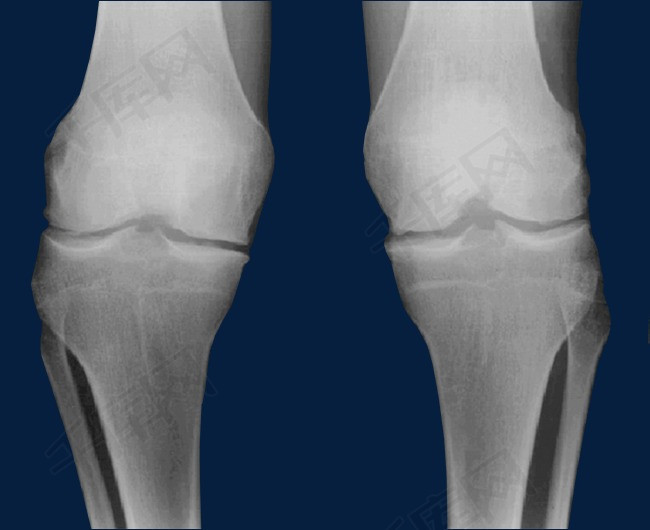

正常人的膝盖骨图片,正常人的膝盖x片图片

正常人的膝盖x片图片

正常膝关节x片

正常膝关节x光片图